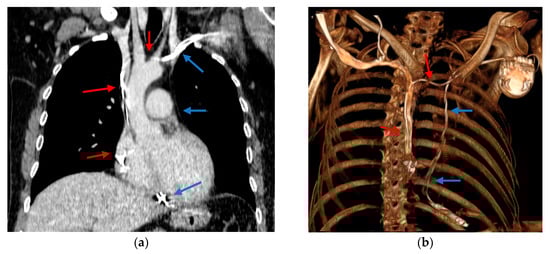

2. Case Report